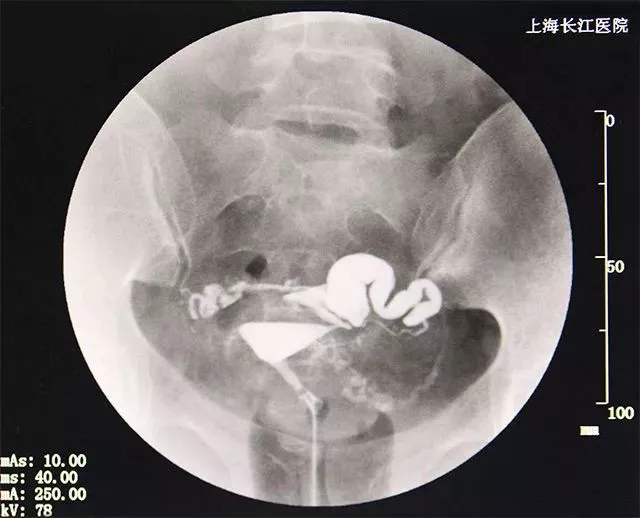

麻烦医生帮我看看我的输卵管造影结果

2013-12-08 晋波 医师 输卵管照影显示~右侧输卵管上举,增粗,扭曲成